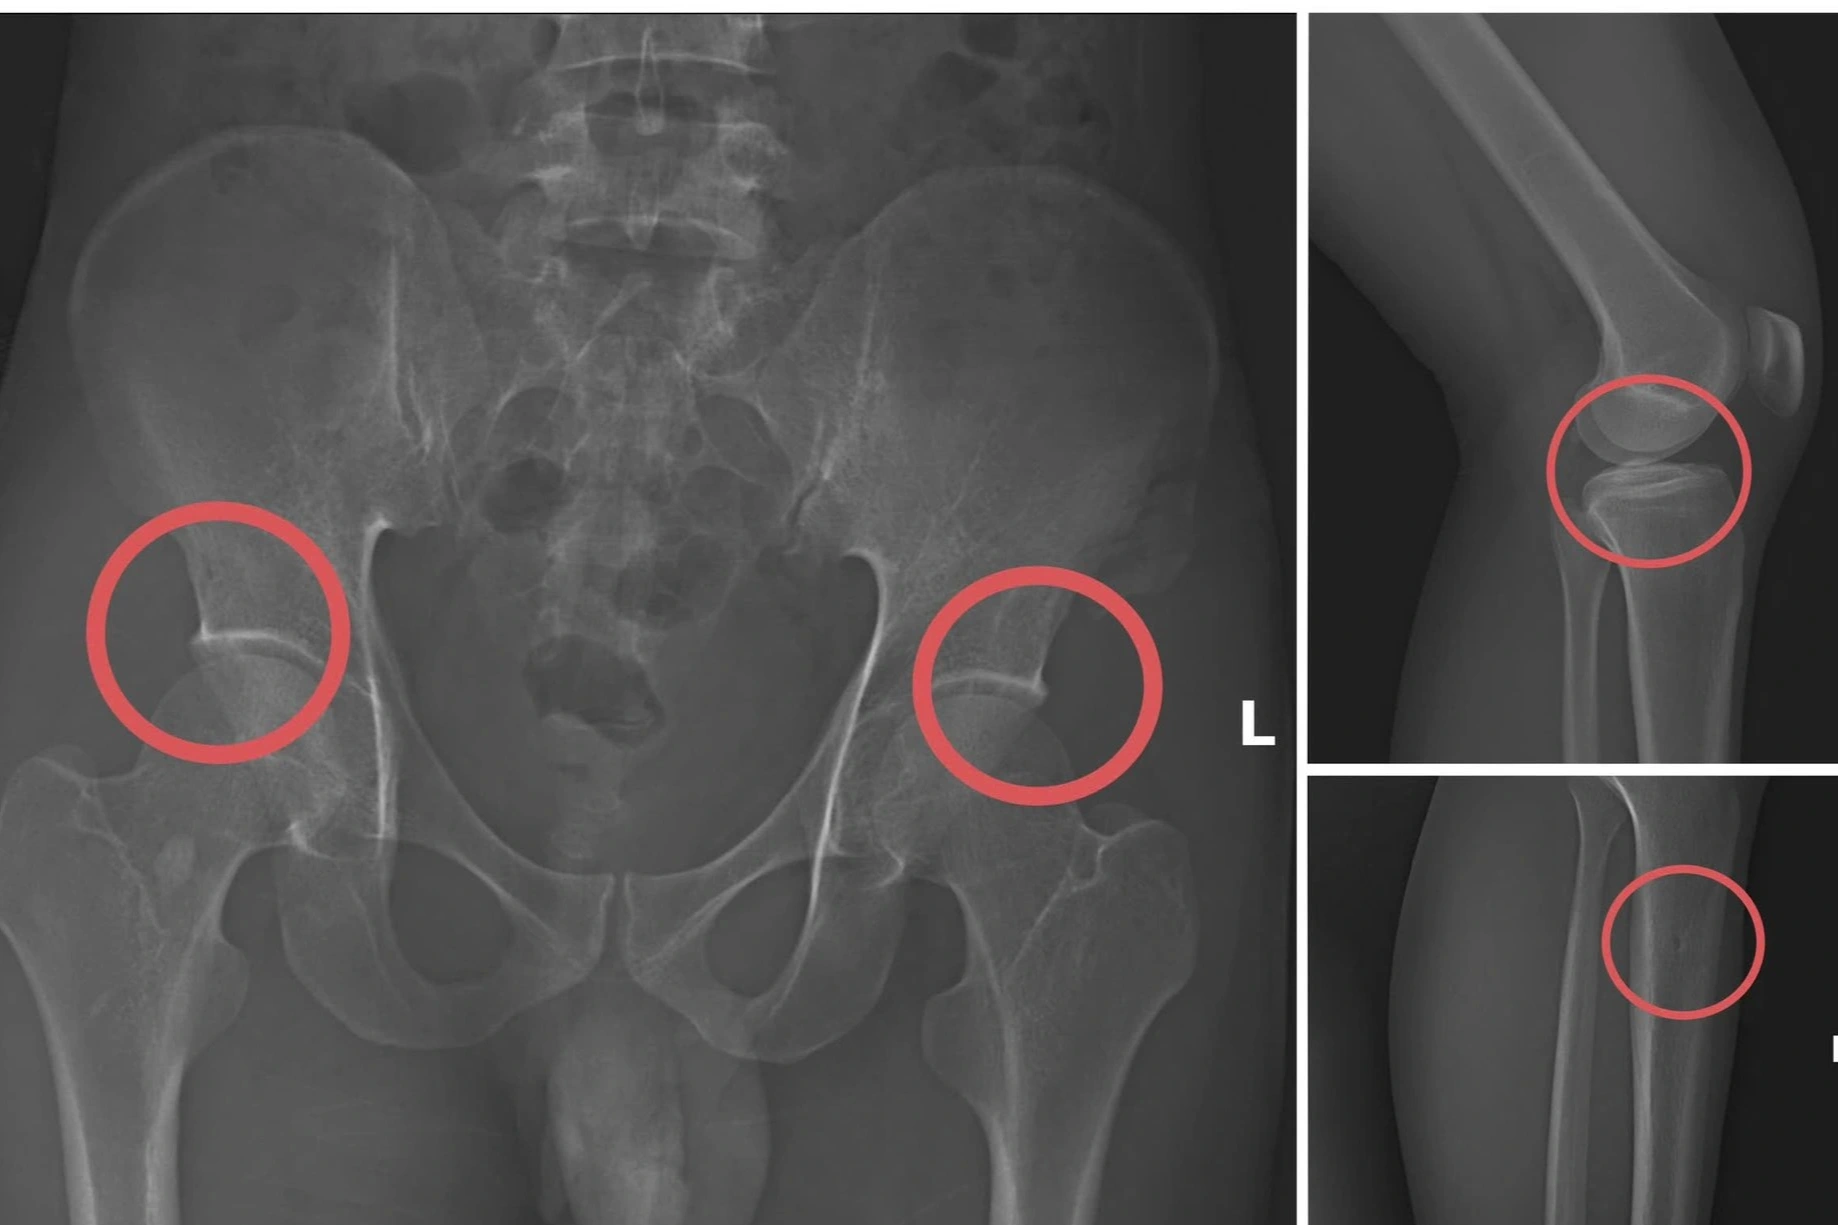

Châu trực tiếp thực hiện hành vi tiêm thuốc mê rồi dùng kim tiêm, búa, đinh để tác động vào xương người mua bảo hiểm, tạo nên các vết nứt, vỡ xương tương tự tai nạn thật.

Giám đốc Công an tỉnh Phú Thọ Nguyễn Minh Tuấn đánh giá thủ đoạn này vừa tàn nhẫn, vô nhân tính, coi thường sức khỏe, tính mạng của người tham gia; vừa được tính toán kỹ để gây thương tích đúng vị trí có mức chi trả cao. Các công ty bảo hiểm cũng khó phát hiện dấu hiệu gian dối.